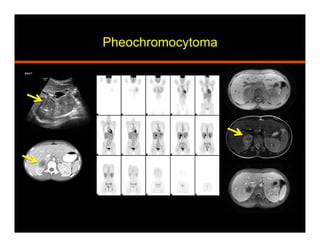

Pheochromocytoma

•  Arises from Chromaffin cells in adrenal medulla

•  Stores and releases catecholamines

•  Elevated serum / 24 hr urine metanephrines

•  Hypertension, palpitations, perspiration and headache

•  10% are: bilateral, extra adrenal (paragangliomas), occur

in children, and malignant (local invasion and mets)

•  Association with syndromes: MEN, NF 1, Von Hippel

Lindau, Tuberous sclerosis, Sturge-Weber

•  CT: homogeneous, well defined, soft tissue attenuation,

avid enhancement with delayed retention

•  MR: T2 bright (light bulb)

•  Take up I123 MIBG, In111 pentetreotide, and F18 FDG

•  Surgical resection

•  Pathology: yellow / tan, hemorrhage, cystic change,

central necrosis, myxoid degeneration. Nest of cells

(zellballen), Salt and pepper chromatin

Metastatic Pheochromocytoma on

F-18FDG PET and I-123MIBG